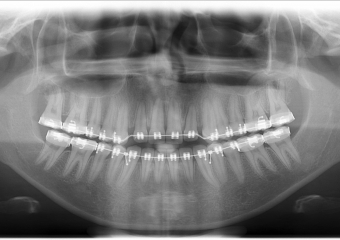

Raio - x Inicial - Clínica Cliniface

Raio - x Inicial

Raio - x após a cirurgia realizada em 2016 - Clínica Cliniface

Raio - x após a cirurgia realizada em 2016